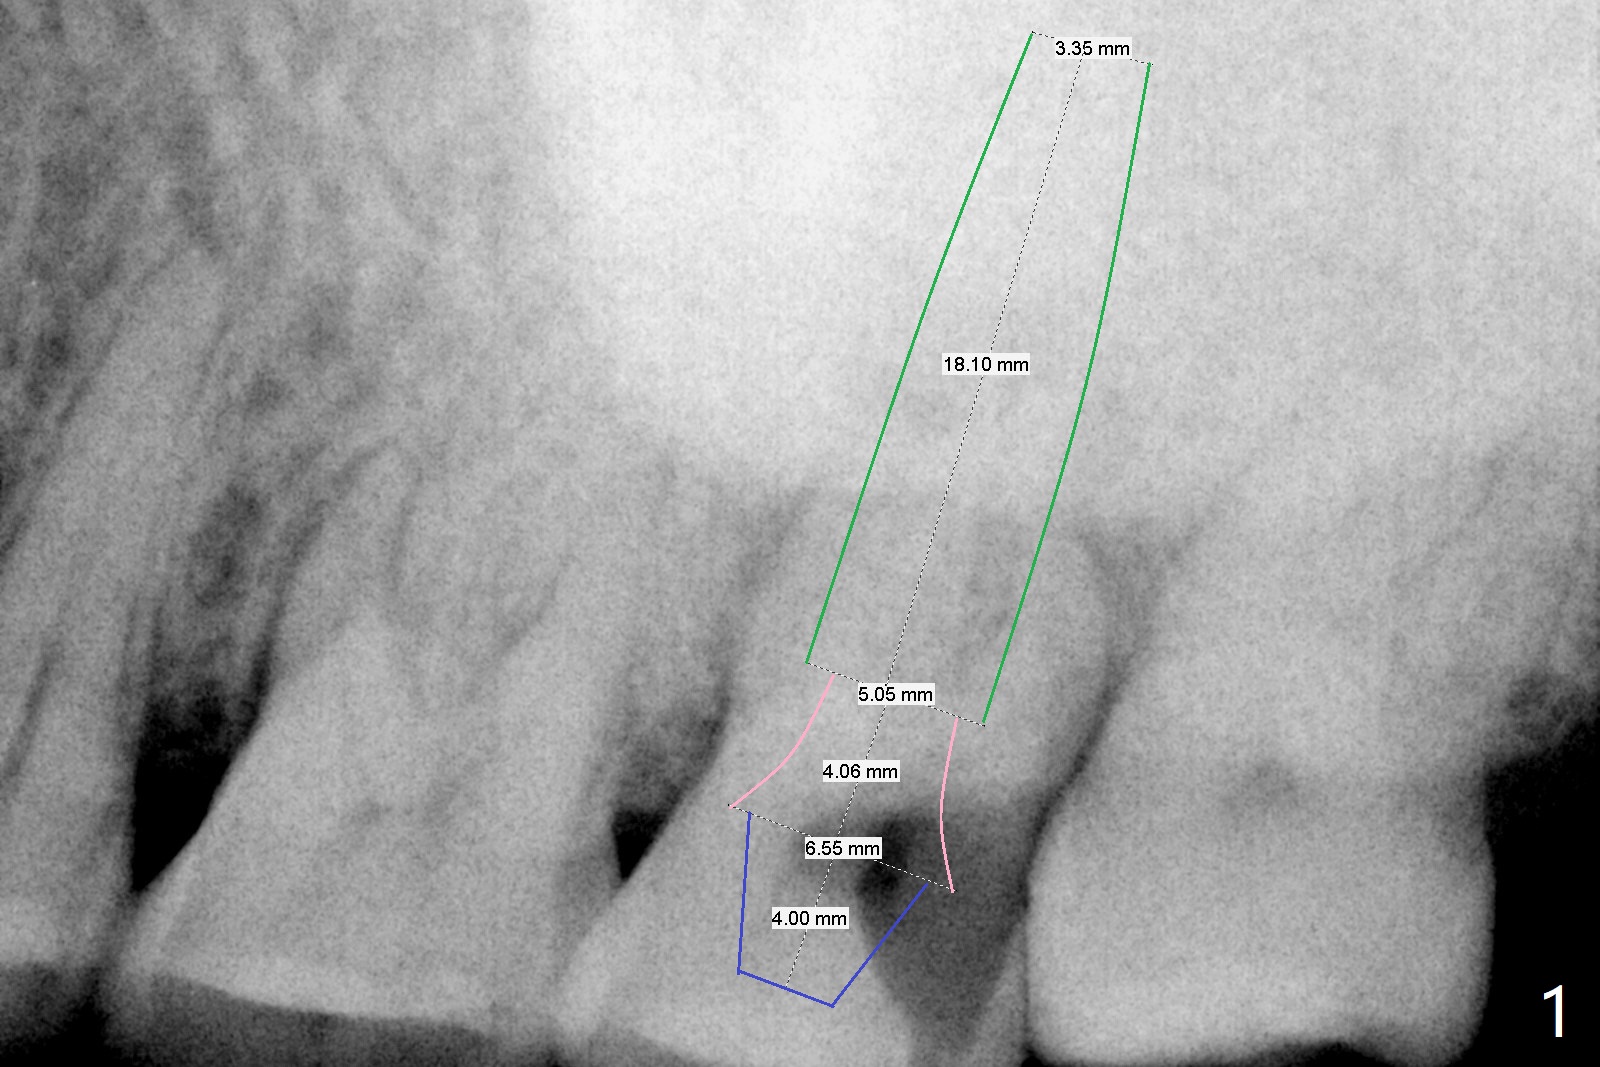

A 59-year-old man had large caries at the tooth #15 in 2009 (Fig.1). There is sign of root fracture in 2014 post RCT (Fig.2, unilateral mastication: #31 missing). Now the affected tooth turns into residual roots with #16 mesial shift (reduced mesiodistal dimension at the edentulous area). A long, relatively narrow implant is to be prepared (Fig.1,2). Take PA preop to confirm that radiolucency is reduced after tooth fracture and residual root coronal displacement.